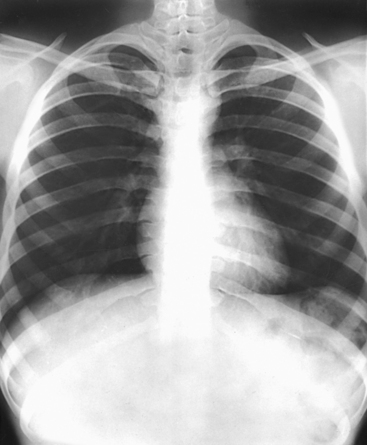

Structures shown: PA projection of the thoracic viscera shows the air-filled trachea, the lungs, the diaphragmatic domes, the heart and aortic knob, and, if enlarged laterally, the thyroid or thymus gland (Fig. 10-32). The vascular markings are much more prominent on the projection made at the end of expiration. The bronchial tree is shown from an oblique angle. The esophagus is well shown when it is filled with a barium sulfate suspension.